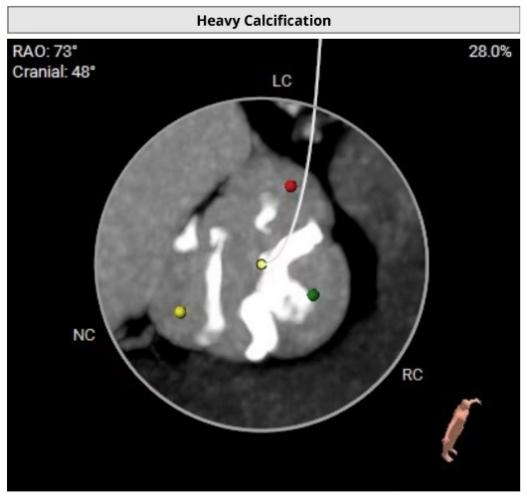

1.该患者为Type-1型二叶瓣。瓣叶略微增厚、重度钙化;

2.钙化主要分布于无冠瓣叶、右冠瓣叶交界,如支架与血管壁贴合不牢,可能会造成较多瓣周漏;

通过充分的术前讨论,翟昌林主任决定使用24mm球囊进行预扩,植入上海微创心通的27# VitaFlow Liberty™瓣膜,使用输送系统自带内联鞘;

该瓣膜径向支撑力适中,能够更好的贴合钙化与血管壁,且独有的10mm双层裙边能够有效减少瓣周漏;

该患者钙化于三个窦内的分布并不均匀,对于释放的稳定性要求更高,VitaFlow Liberty™全球独有的电动释放输送系统,在释放瓣膜时能够更精准的操控,提升瓣膜释放过程的稳定性;